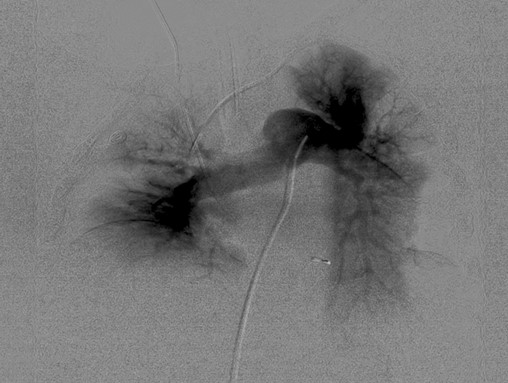

EKOS1 uses a catheter system to deliver clot-busting medicine directly to the embolism, at the same time using ultrasound energy to loosen the clot and allow the drug to permeate the clotting strands, increasing the thrombus surface area and letting the drug reach more plasminogen activator receptor sites. The use of ultrasound permits a lower but equally effective drug dosage. Compared to other endovascular techn

iques to treat PEs, EKOS reduces treatment time and the lytic dose, ultimately lowering cost and the risk for related bleeding complications.

Two EKOS catheters are in place, one in each lung, during the treatment of a PE. Images courtesy of Timothy Smith, MD.